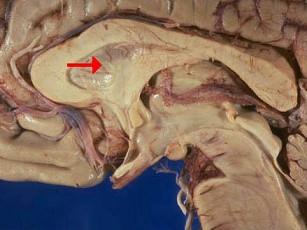

问题 如图箭头所示为大脑哪个部位 ( )

选项 A、第三脑室 B、中脑导水管 C、透明隔 D、屏状核 E、脉络丛 一、单项选择题

答案 C